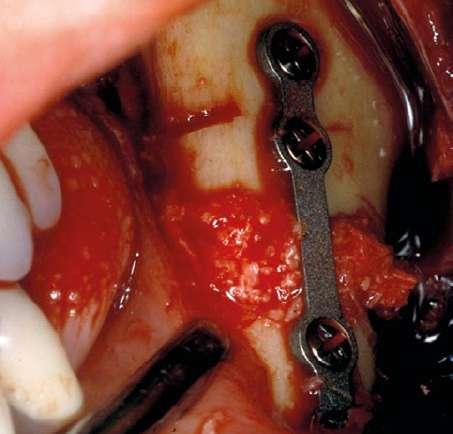

La cirugía ortognática se realiza bimaxilar, procediéndose al avance del maxilar superior y la retrusión de la mandíbula. En las imágenes intraquirúrgicas vemos el gran avance realizado en el maxilar superior y la distancia que se pretende reducir en la mandíbula mediante una osteotomía sagital deslizándose las corticales una sobre otra para conservar intacto el canal del nervio dentario (figuras 9-12).

Figuras 10 y 11. Inicio de la osteotomía mandibular y finalización de la misma con la colocación de la mini-placa de fijación y relleno del gap con hueso autólogo particulado (triturado del fragmento óseo retirado) unido al PRGF-Endoret.

Figuras 13-16. Imágenes de retirada de las miniplacas de la mandíbula donde podemos observar la regeneración ósea completa de la zona donde se produjo la osteotomía sagital.